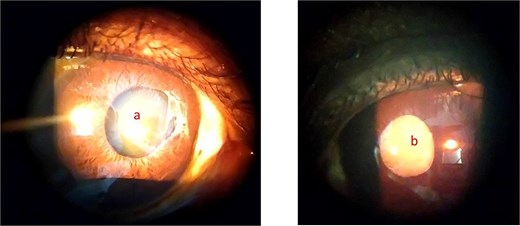

On ophthalmic examination with slitlamp biomicroscope the patient had iris atrophy with torn iris sphincter nasally in the right eye and mid dilated as well. The lens in the right eye was clear using LOCS III grading (Fig. 4a). The left eye had a complicated cataract, and this obscured the view of the fundus (Fig. 4b). There were vitreous tractions at the macular (Fig. 5) and black sunbursts lesions in the peripheral retina in the right eye during funduscopy.

Showing anterior segment photograph of the right eye with iris atrophy (a) and complicated cataract in the left eye (b).